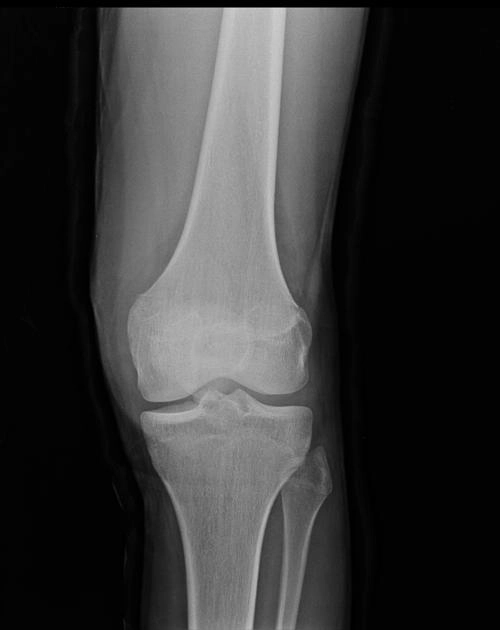

• Tổn thương xương và khớp gối

Gãy mâm chày (Tibial Plateau Fracture)